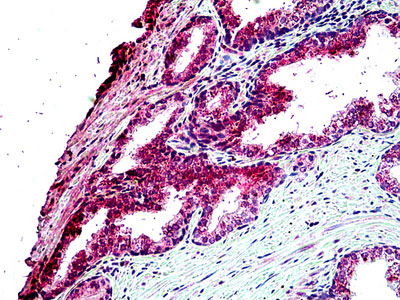

Anti-TBC1D10A antibody IHC of human liver.

Anti-TBC1D10A antibody IHC of human prostate. |